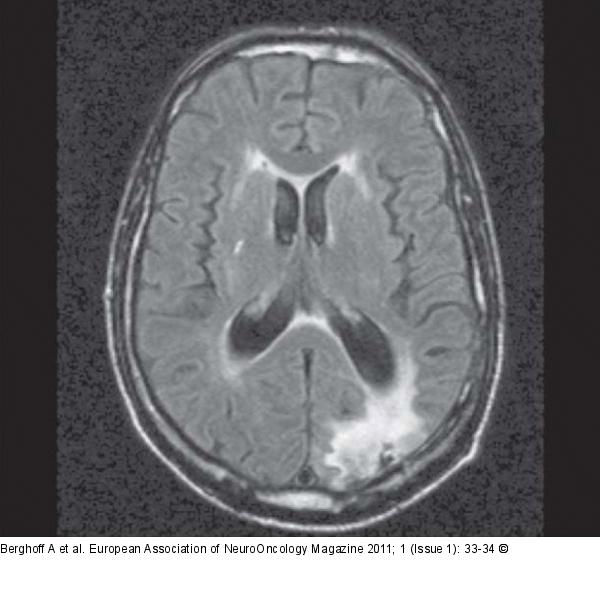

Berghoff A, Furtner J, Wöhrer A, Gatterbauer B, Dieckmann K, Preusser M

Management of Brain Metastases: A Case Study

European Association of NeuroOncology Magazine 2011; 1 (1)

: 33-34

Figure/Graphic 4: FLAIR-MRI

Axial FLAIR-MRI